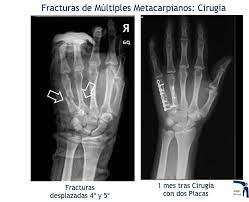

Las fracturas en los pequeños huesos de la mano podrían sanar bien siempre y cuando el daño no sea muy grave. Una quebradura de muñeca es una fractura o fisura en uno o más huesos de la muñeca. 2012 Descripción Educación Común y modalidades Educación Especial y Educación de Jóvenes y Adultos.

Código lum000133 Título Horas cátedra por modalidad oferta educativa y sector de gestión según departamento. Si la fractura daña el tendón o el ligamento la curación puede durar aún más. Fuente Relevamiento Anual 2012. Cuánto tiempo dura la rehabilitacion de. Fisuras Cirugía de aparato digestivo Cuánto tiempo se necesita para que funcionen los. Completa donde el hueso se rompe en dos tallo verde donde el hueso no ha completamente roto pero es roto en un lado solo donde el hueso se rompe en un solo lugar conminutas donde el hueso se ha roto o se rompe en varios pedazos y abierta donde el hueso está roto tan severamente que. Las fracturas en los pequeños huesos de la mano podrían sanar bien siempre y cuando el daño no sea muy grave.